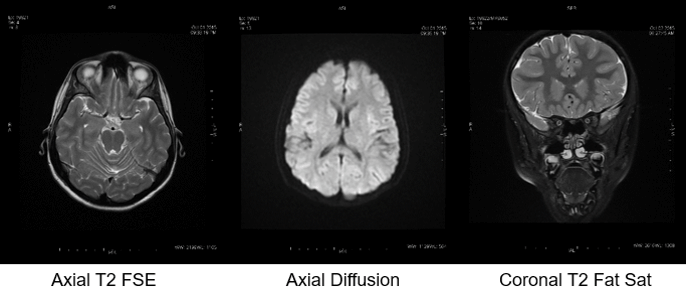

Here we are looking at a variety of different ways to show T2 weighted contrast. In the first image, we have an Axial (which tells us which plane we have acquired the data) T2(which tells us which tissue contrast we have acquired), and the acronym FSE (which tells us that it is a Fast Spin Echo). The second image is also an Axial, and it is T2 weighted, however, it is a diffusion scan which is producing an image that takes into account how well the brain tissue is diffused with blood. As you can see they look quite different and are showing us very different information.

The last image is also a T2 weighted image, however, it is a coronal and we have applied a Fat Saturation pulse to the sequence. If you look closely around the skull on the first and last images, you can see the fat surrounding the skull is NOT visible on the last image, and it is visible on the first image. Remember, T2 weighted images are heavy on T2 contrast.